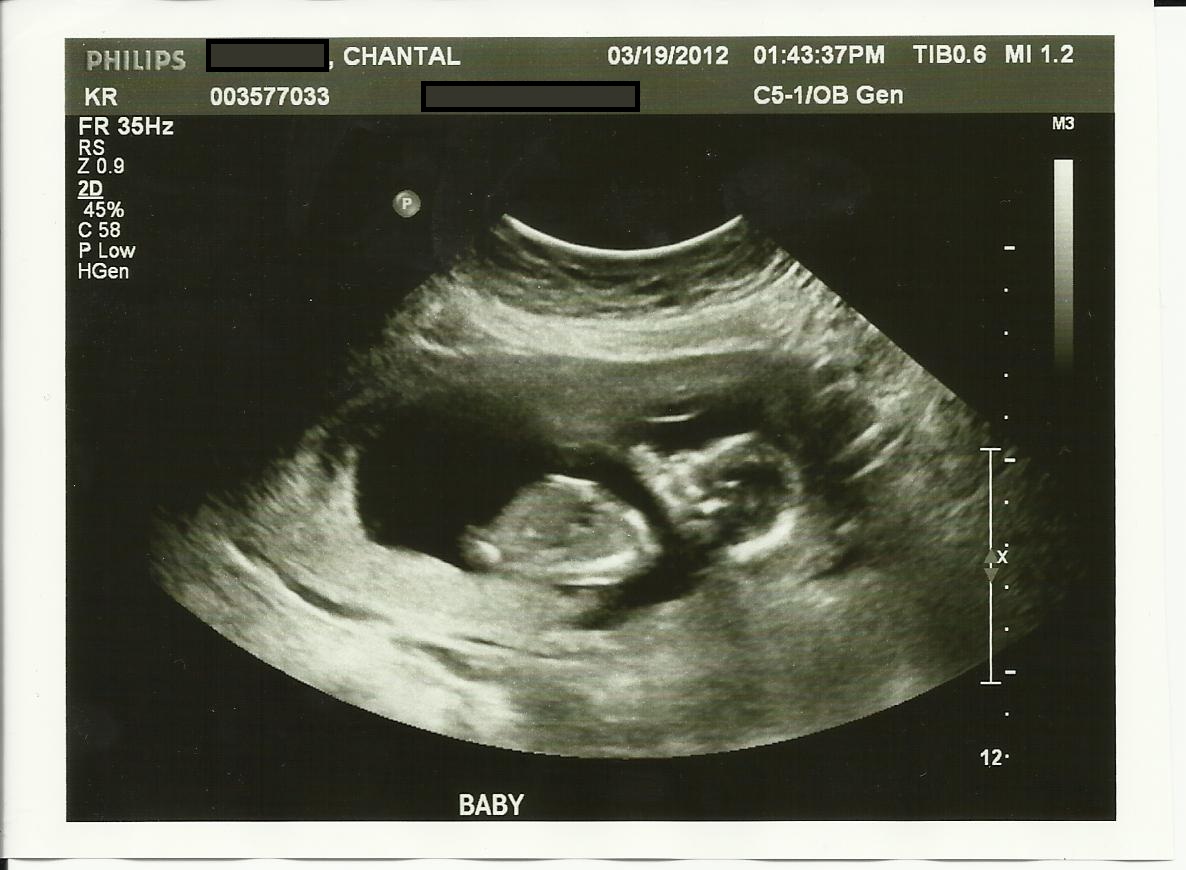

Skull guess please!

This is my ultrasound from 13 weeks 5 days. The tech did a quick crotch shot, but wouldn't look too hard. I am studing to be a Radiologist and I know that I for sure didn't see a nub.

Any guesses on the skull?? To me, the skull and chin look more female like, especially compared to my son's ultrasound photos!

Attachment 1763Attachment 1764Attachment 1765

I think the nub looks like a girl.

Do you mean you didnt see a willy in the potty shot? I see the nub in your first pic, it does look girly.